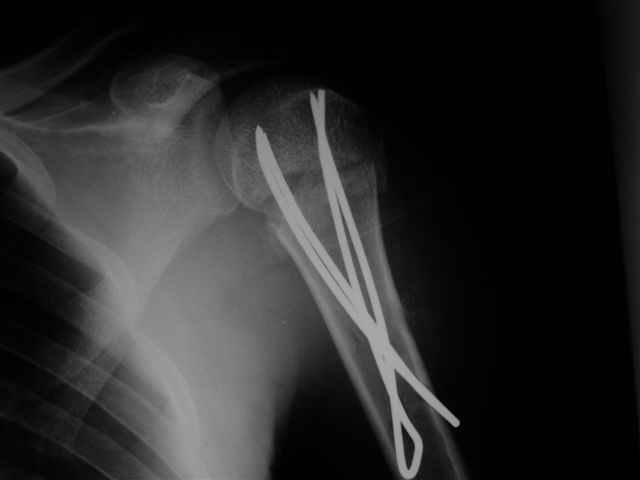

Посылаю послеоперационные Рг граммы.

Поздравляю, получилось просто замечательно. Если можно, расскажи чуть подробнее, как делали - как вправляли, как вводили спицы, поворачивали ли их?

Я и сам доволен результатом. В предпоследнем письме я кратко описал ход операции - закрыто репонировать не удалось( 2 недели с момента травмы и 1 неделя после неудачной репозиции) после удаления пучков спиц, пришлось сделать - 2см разрез на уровне перелома и с помощью периостального элеватора (золотое правило механики) *одеть* головку на дистальный отломок.

Спицы проводил через старые отверстия, вращая пучок импактором- направителем при его введении в головку.